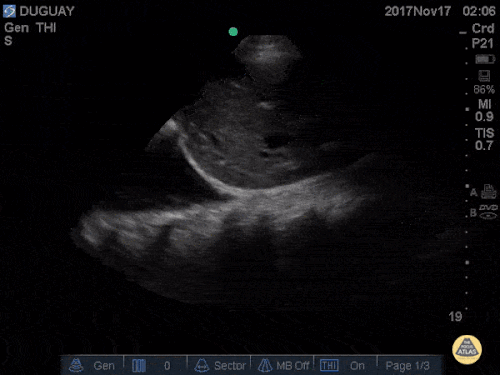

Question 1: A 50-year-old patient presents with dyspnea. fever, and cough. He started feeling poorly yesterday and has deteriorated steadily since then. His blood pressure is stable and he is requiring two liters of oxygen to maintain his saturation. This is the thoracic ultrasonography, starting at the diaphragm and moving upwards.

This is the ultrasound view with the probe held in place at the base of the lung.

- What radiographic finding does this correlate with on chest X-ray or CT scan?

- What are the most common causes of this type of radiologic pattern?

- What diagnosis do you think this patient has? Please try to be as specific as possible.

- What therapeutic regimen would you prescribe?